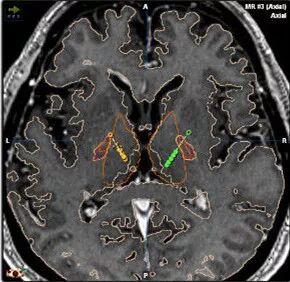

DBS手术是一个要求非常精准的手术,术中需要正好定位到相对应的大脑核团。在美国的时候美国的医师更多的选择GPI核团,国内选择STN核团的更多。

患者入院后,需要做相应的术前检查和术前各项评估。在手术前一天需要做头颅磁共振检查,以便根据影像学检查结果制定相应的手术导航计划。

手术当天给患者安装好头架后做CT检查。

整个手术,我们通过术前计划系统、术中微电极记录、患者术中的症状缓解和植入后复查的影像学资料,4个方面保证电极精确的植入在相应的核团上。